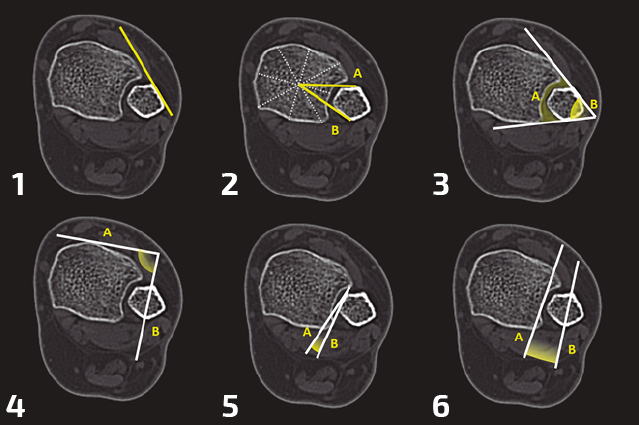

Existen multitud de técnicas de medición en TC descritas en la literatura (Figura 2). Al igual que ocurre con las radiografías simples, existen variaciones morfológicas (incluso se ha publicado la morfología más frecuente en lesiones de sindesmosis)(29) que restan validez a las mediciones(15). Sin embargo, variaciones respecto al tobillo contralateral > 2,3 mm de espacio tibiofibular o rotaciones > 6,5° del peroné se consideran patológicas(15). Es de capital importancia que estas medidas se realicen al mismo nivel del tobillo en cada lado.

Figura 2. Métodos de detección de desplazamiento o malreducción tibiofibular. 1: línea tibiofibular. Línea que prosigue la superficie plana anterolateral del peroné. En tobillos normales contacta con el tubérculo anterior de la tibia; 2: relación de la distancia que existe entre el centro de la tibia con la cortical anterior y la cortical posterior del peroné. Se compara con la contralateral; 3: el ángulo formado por la línea tangencial de la cortical anterior con la posterior y el área contenida entre este ángulo y la tibia y el peroné se comparan con el tobillo contralateral; 4: el ángulo formado por la línea tangencial de la superficie tibial anterior y la línea de bisección del peroné se comparan con el contralateral; 5: ángulo entre la línea tangencial del borde medial del peroné y la línea de la incisura tibial. Se compara con el contralateral; 6: ángulo formado entre la cara posterior de la incisura tibial y el eje del peroné.